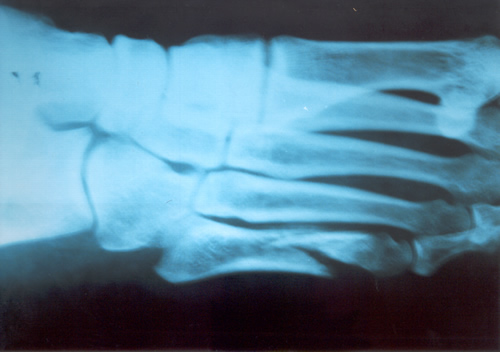

FRACTURA DEL QUINTO METATARSIANO

Generalmente la informamos como fractura de la cola del quinto metatarsiano, porque allí es el lugar de mayor frecuencia, especialmente en el deportista saltador. En nuestro estudio estadístico y para el libro de Traumatología en el Futbol ( edición 2005 Ed Akadia,)

observamos que la mayor cantidad de estas fracturas, fueron padecidas por los defensores centrales , atribuible esto al mecanismo de acción en el salto en ambas áreas, correspondiente a la función de dicho jugador. El caer, frecuentemente se genera una torsión en supinación en el momento de apoyar con la cara externa del pié, ora en terrenos desiguales ó bien con pérdida de la estabilidad en el aire, debido a la fricción con el contrincante.

Dicha caída desarticulada produce un esguince de antepié, con impacto sobre la cola del quinto y fractura secuelar. Puede escucharse ruido con dolor puntual, por lo que el jugador abandona el campo de juego.

En la generalidad de los casos, con una inmovilidad adecuada sin cargar el peso del cuerpo por 45 días suele consolidar la fractura. Depende del trazo de la fractura y en que lugar está ubicada en el hueso Dicho metarsiano presenta una irrigación sanguínea deficiente y es quizás la causa importante que impide consolidaciones seguras y en poco tiempo. Aún mas, si ocurre en un pié cavo varo, es decir en un pié con mucho arco interno distinto ú opuesto al apoyo anatómico del pié plano. Este es el jugador que padece esguinces a repetición de tobillo por exceso de arco del pié.

Si la fractura se ubica en el tercio medio de la diáfisis del hueso , ya no en la cola del quinto, el tratamiento incruento generalmente es exitoso. En nuestro caso y para esta patología nos estamos ocupando sólo de la cola del quinto.

Sin embargo, puede ocurrir que luego de la inmovilización sin apoyo del pié lesionado, y que el informe de las imágenes radiográficas y tomográficas, no demuestren un callo aceptable para el comienzo de la rehabilitación kinesiológica, está la posibilidad de la resolución quirúrgica.

También ésta, presenta dos alternativas. O bien disconforme con la imagen que arrojan los estudios se indica osteosíntesis de aquella mediante un tornillo ó bien si intentan con rehabilitación kinesiológica post inmovilización, recuperarlo a pesar de un callo endeble, puede ocurrir que no se logre lo deseado.

En este caso, si el jugador en varios intentos de probar en el campo de juego siente dolores o se genera dolor parecido al inicial luego de caídas repetidas, estaremos en presencia de un déficit de consolidación por retardo de la misma ó peor aún, seudoartrosis ó falsa articulación ó movimiento indeseable en el foco de la fractura que impide la total recomposición de la misma.

En este estadío es cuando no cabe duda que la indicación es la operación . Personalmente nosotros hemos realizado osteosíntesis con tornillo junto a injerto óseo en el lugar lesionado que es extraído de la cresta ilíaca de la pelvis. Elemento óseo éste con gran irrigación sanguínea que viene a alimentar el déficit del hueso metatarsiano. Siempre utilizamos inmovilización enyesada por 45 días. Habrá quien utilice ortesis y ello depende la casuística de cada cirujano. Pero esto ya es tema para otro artículo.